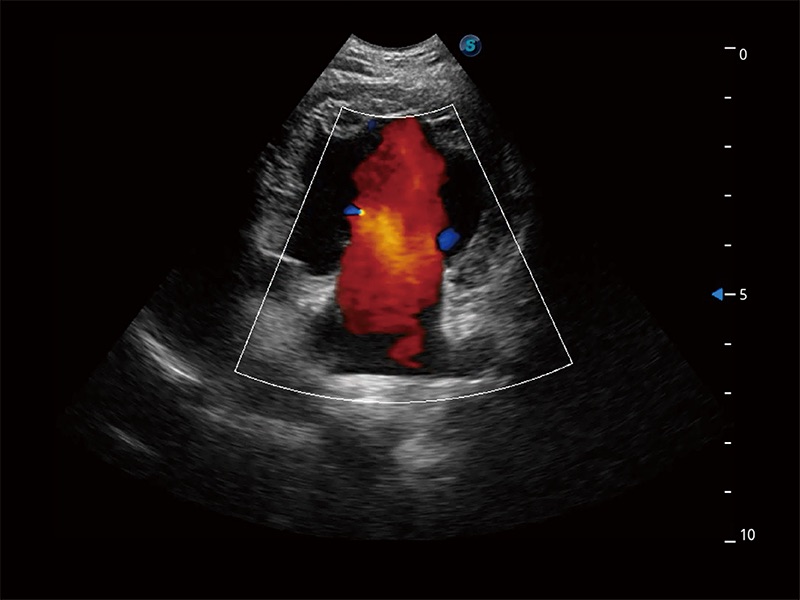

Ausgestattet mit dem gesamten Sortiment an Phased-Array-Schallköpfen von SonoScape (S1-5, 7P-A, 8P1), hochentwickelter Verarbeitungstechnologie und modernsten kardiologischen Tools bietet die ProPet-Serie Tierärzten eine umfassende ABklärung der Herz- und Myokardfunktionen.

Nutzt myokardiale Doppler-Frequenzverschiebungen zur Quantifizierung der myokardialen Gewebebewegung, wobei Rot und Blau die unterschiedlichen Bewegungsrichtungen der Herzwände darstellen. Durch die Kombination von TDI und PW lässt sich die Bewegungsbahn der Myokardwand besser erfassen.